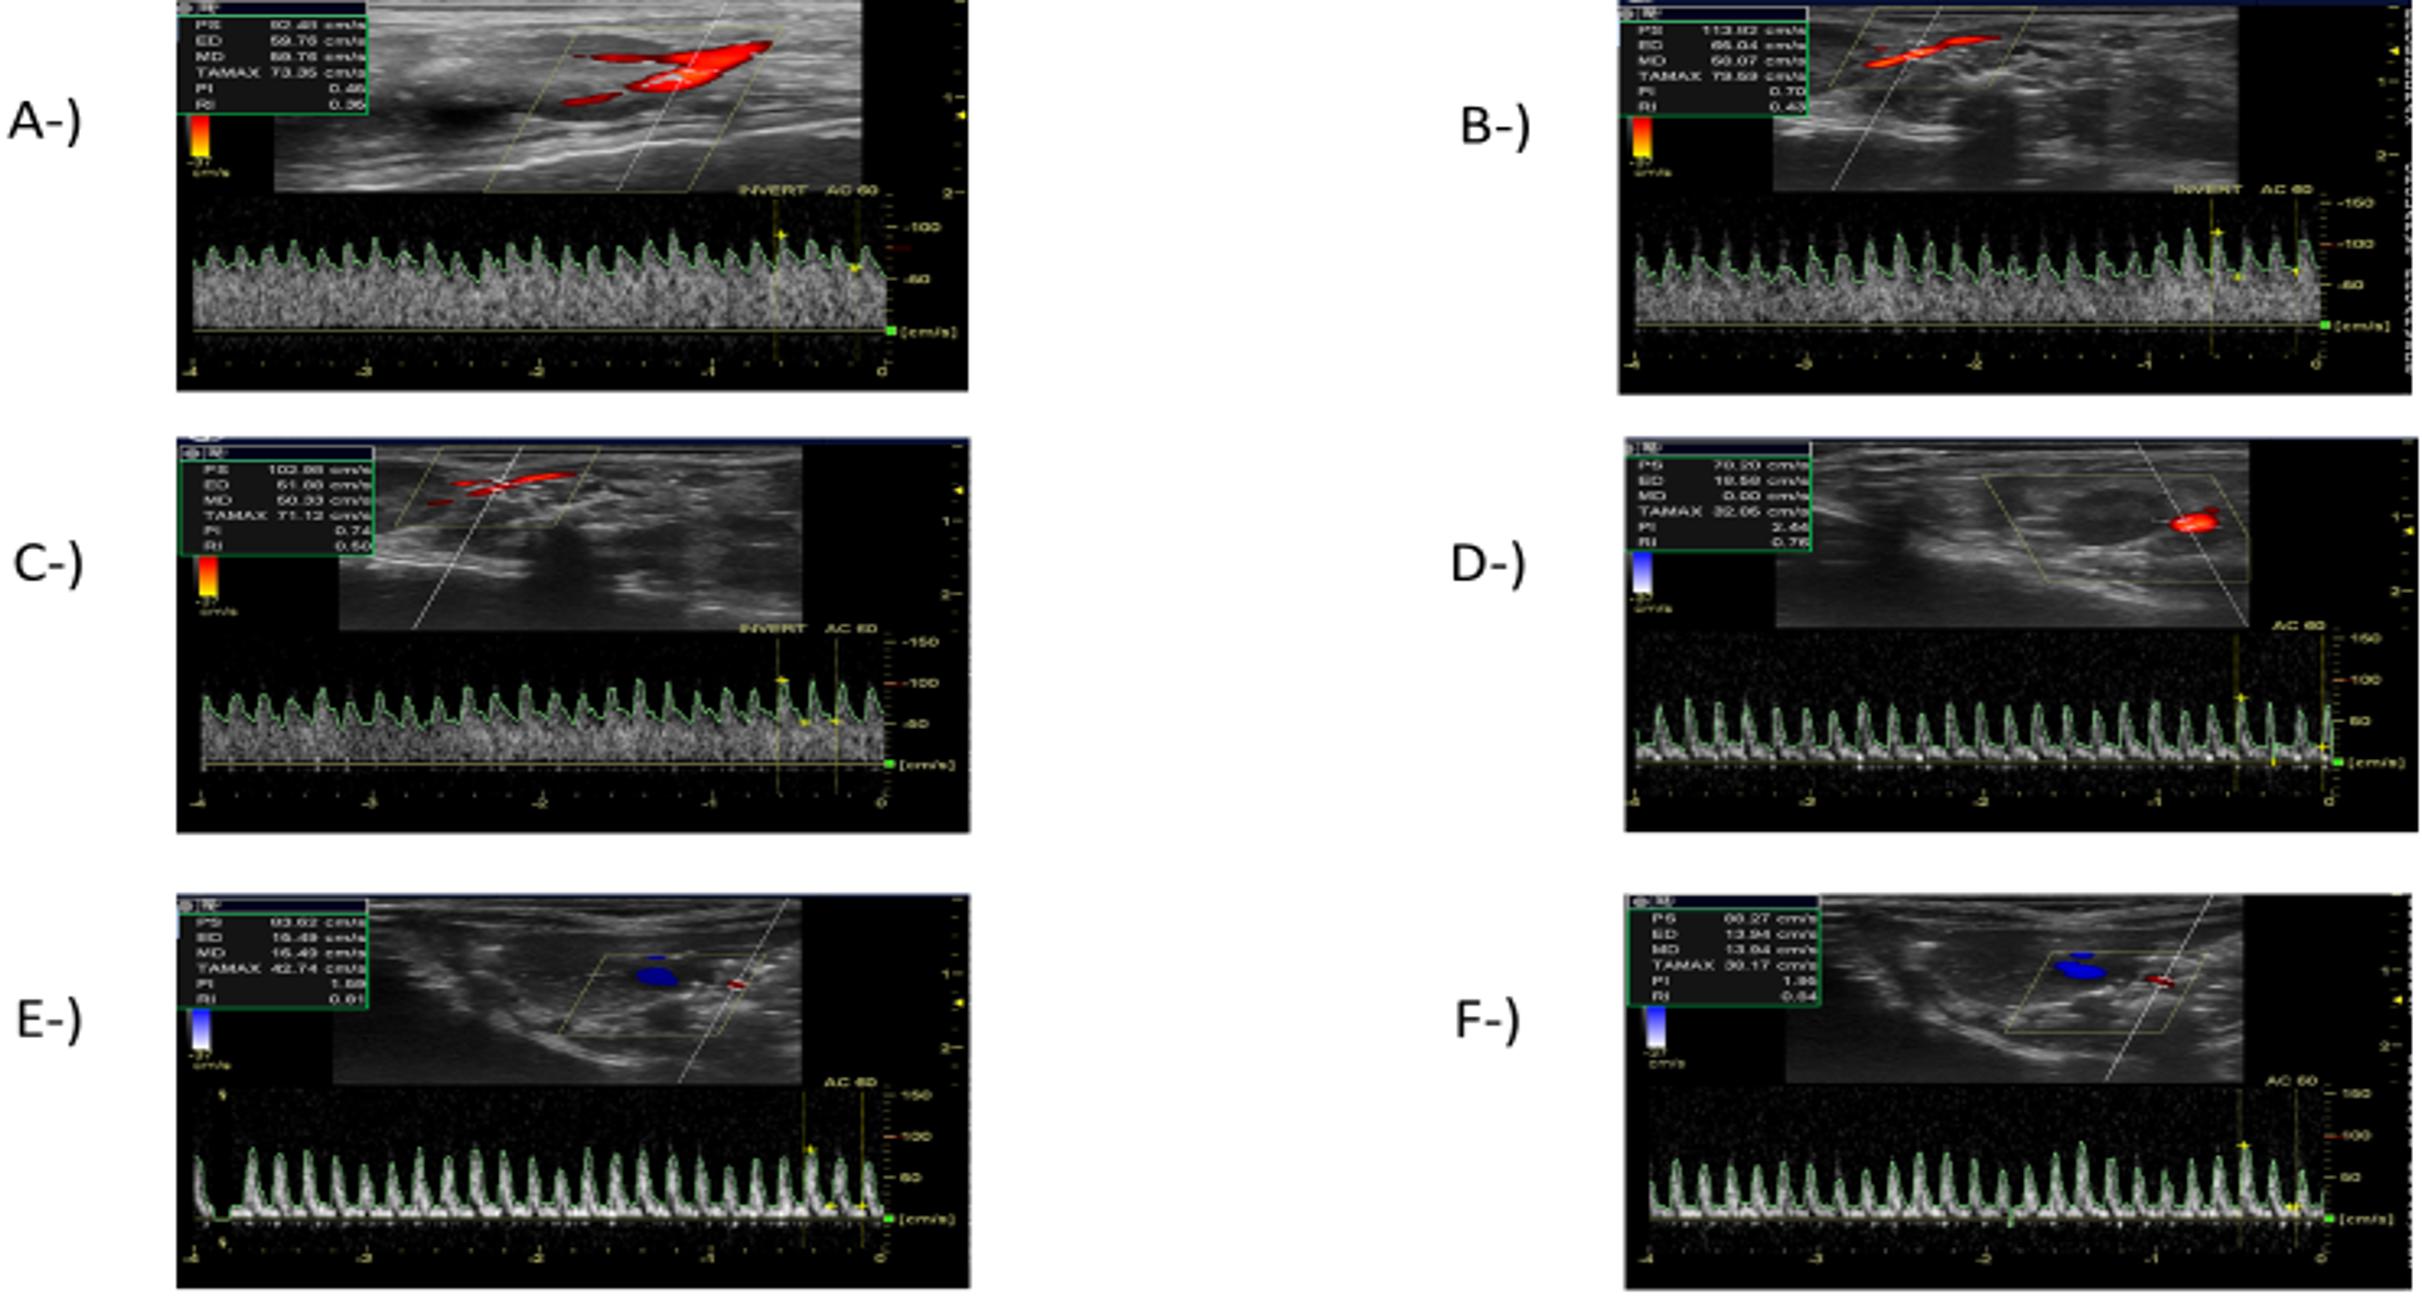

A linear transducer (12 MHz, GE, Logiq e, USA) was used for the sonographic examination, with the “vascular imaging” option preselected. While the experimental animal was in the supine position, the probe was inserted in the transverse plane through the midline to acquire images of the aorta. The platform was then shifted together with the animal to reach the level of the renal artery. The color Doppler mode was used to acquire images of the renal artery and renal vein. The (PW) pulsed-wave mode was used to evaluate blood flow in the renal artery. The indicator line in the PW mode was brought to the renal artery in the flow direction. Typically, three to five arterial signals were acquired from the renal artery. The appearance of the waveform was optimized using the lowest pulse repetition frequency and the highest possible gain. The images of the waveforms indicating the velocity of the flow in the artery at peak systole and diastole were acquired, and RRI was calculated using the following formula:

RRI = (PeakSystolicVelocity – EndDiastolicVelocity) / PeakSystolicVelocity

RRI was evaluated using a renal Doppler USG, 3, 6, 12, 24 and 48 hours after the CLP procedure. RRI started increasing 3 hours (0.38 ± 0.07) after the CLP procedure when compared to the sham group (0.36 ± 0.03), while the increase in RRI started to become significant at 6 hours (0.44 ± 0.04) and peaked at 24 hours (0.73 ± 0.02) after the CLP procedure. Although the increase in RRI tended to decrease at 48 (0.66 ± 0.15) when compared with the mean value at 24 hours (0.73 ± 0.02) after the CLP procedure, the difference was not statistically significant (p>0.05) (Figure 1). The RRI measurements in the sham group and at different time points after the CLP procedure are presented in Figure 2.

In this rat model of sepsis, RRI was measured at 3, 6, 12, 24 and 48 hours after the CLP procedure to identify any impairment in renal circulation in the early period, which is considered an early sign of SI-AKI (11,14). Increases in RRI values were noted starting at 3 hours after the CLP procedure, and this increased to reach statistical significance at 6 hours. As reported by Song et al. in a study of human subjects evaluating the ability of RRI to detect SI-AKI in the early period, the pulsed-wave Doppler spectrum of the AKI group showed a narrow and steep waveform character that resulted in a high RRI value, similar wave forms were noted in the present study, becoming narrow and spiky, and with an increase in RRI that paralleled the degree of kidney injury(21). The present study also identified a strong positive correlation between RRI values and the degree of tubular damage in a histopathological examination. The authors believe the change in RRI to be a result of the greater decrease in diastolic blood flow than in the systolic blood flow, which we attributed to the increase in renal vascular resistance caused by sepsis induced-inflammation and the impairment of microvascular functions.